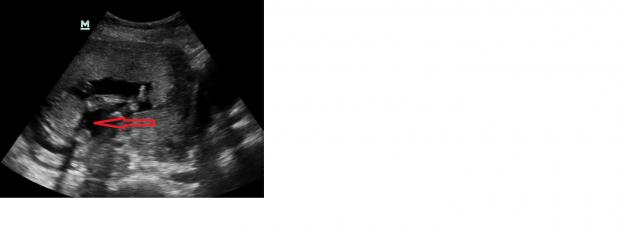

Attachment 18743

Can you se something on this pic? Also från the ultrasound :)

I see a snail shape (I.e. penis & scrotum) repeatedly. Looks quite boyish to me, but not so clearly that I'd bet money or announce.